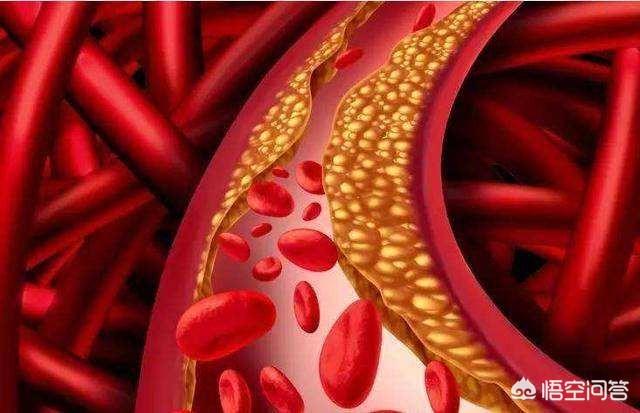

高脂血症などの心血管危険因子の影響により、血管の内壁は徐々に傷つき、血液中の余分な脂質は徐々に血管壁の下に沈着し、黄色い粥腫性脂質コアを形成し、最終的には脂質コアに線維性被膜が形成され、これが動脈プラークの形成過程である。 プラークは動脈硬化を引き起こす危険因子であり、安定性や破裂に問題のあるプラークは、反応性血小板血小板の反応性凝集は血栓を形成し、動脈血管を閉塞させ、梗塞性心血管病を引き起こすことさえある。したがって、私たちはプラークの問題に注意を払う必要がありますが、通常、すでに形成されたプラークを元に戻したり除去したりすることは非常に困難であり、私たちがしなければならないことは、合理的な薬物療法と運動によってプラークの形成を予防し、既存のプラークに対して、プラークの安定性を維持するように努め、動脈硬化のプロセスを遅らせ、プラークの破裂がより大きなリスクを引き起こすのを防ぐことです。

プラークは、静脈プラーク、動脈プラークを持って、それは複数の病因因子の役割にある、沈殿物の脂質化のために、単刀直入に言えば、つまり、あなたがより多くのグリース、消化と使用することはできません、血中脂質4と他の多因子の影響下で、内膜に損傷を与え、血管の内層に沈着し、黄色のアテローム性脂質のコアの形成、および最終的に線維性キャップが持続的な炎症にさらされている場合、通常は非常に安定している脂質のコア、上の線維性コアの形成にある攻撃は、飲酒、怒り、夜更かし、少ない水を飲むなど、線維性キャップが破裂し、プラークが流出し、血液中の血小板が結婚フラッシュ、血栓と呼ばれるトラブルメーカーの子供を出産し、この子は、血管をブロックするために悪いことをすることに特化し、トラブルを作るためにさまよう、血管の内腔に血栓が同時に狭くなるだけでなく、破裂、急性心脳血管イベント、脳卒中、心筋梗塞、肺塞栓症、腎不全、静脈瘤などを誘発する。などである。したがって、プラークを除去することは、血管の詰まりを取り除くだけでなく、急性心血管系および脳血管系イベントを予防することにもなり、誰もが関心を寄せている。

動脈プラークは、複数の病因因子の影響下にある動脈内膜の損傷によって引き起こされる一連の炎症反応であり、後に二次的なアテローム性プラークが生成される。プラークの形成は人体にとってより有害であり、同時に血管の内腔を狭くし、破裂して急性心血管系イベントを誘発することもある。したがって、プラークを除去することは血管の詰まりを解消するだけでなく、急性心血管系イベントを予防することにもなり、これはすべての患者の心臓の鼓動である。プラークの治療には、血中脂質、血圧、血糖値などのコントロール、減塩、低コレステロール食、運動量の増加、禁煙、アルコール制限などの悪い生活習慣の改善など、病気の原因から始めるか、上記の治療の上に薬物療法を行うことができます。薬の選択は、アトルバスタチン、レセルプルバスタチンなどのスタチン系薬剤がアテローム性プラークの治療によく使用されます。具体的な治療計画は専門医の指導のもとに立てるべきである。

アテローム性動脈硬化症は、成人であれば思春期から誰もが経験する動脈血管の内皮病変である。数十年かけてゆっくりと進行し、最終的にはアテローム性動脈硬化斑を形成して血管を詰まらせたり、破裂させたりして、脳出血、脳梗塞、冠動脈疾患、大動脈瘤の分離などの重篤な心血管・脳血管疾患を引き起こす。

プラークが発生する過程にはいくつかの段階があり、まず血管の内皮が傷つき、血管内面の保護層が「壊れる」ようになると、血液中の高分子脂肪が低比重リポ蛋白と呼ばれる一種の物質によって血管壁の内膜中膜層に大量に運ばれて蓄積し、血管壁が肥厚し、医療では内膜中膜層が1mm以上になると動脈硬化が起こっていると言われています。内膜中膜層の肥厚が1mmを超えると、局所的に凝集して塊になったような動脈硬化、すなわち初期プラークが生じたといわれる。

初期のプラーク形成は、脂肪の蓄積が一連の炎症反応を引き起こし、実際には、脂肪は常に酸化変性、粥状物質の形成であり、これらの物質は、血管の正常な構造を破壊し、血管の一部となり、この時点で、脂質化された材料は、通常、ソフトスポットと呼ばれる液体の状態にほとんどである。